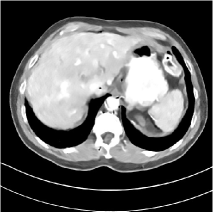

Refer to caption WavResNet [11]Refer to caption WavResNet [11]Refer to caption WavResNet [11]Refer to caption Momentum-Net (SimpleCNN)Refer to caption Momentum-Net (SimpleCNN)Refer to caption Momentum-Net (SimpleCNN)Refer to caption Momentum-Net (SimpleCNN-RSN)Refer to caption Momentum-Net (SimpleCNN-RSN)Refer to caption Momentum-Net (SimpleCNN-RSN)Refer to caption Momentum-Net (Dn-RSN)Refer to caption Momentum-Net (Dn-RSN)Refer to caption Momentum-Net (Dn-RSN)Refer to caption ReferenceRefer to caption ReferenceRefer to caption Reference

Refer to caption Refer to caption Refer to caption Refer to caption Refer to caption Refer to caption Refer to caption Refer to caption Refer to caption Refer to caption Refer to caption Refer to caption Refer to caption Refer to caption Refer to caption

Fig. 3: Three examples (from top to bottom) of the reconstructed testing images using Momentum-Net with SimpleCNN (the second column), with SimpleCNN-RSN (the third column), and with Dn-RSN (the fourth column). The compared WavResNet denoised images are shown in the first column, and the reference images are in the fifth column. See their FBP images in Fig. 4.

Fig. 2 shows that the proposed Momentum-Net with SimpleCNN decreases RMSE dramatically in the first 30 layers, and tends to converge in 50 layers. The Momentum-Net reduces the mean RMSE value by 4.5 HU and gives smaller standard deviations in RMSE, compared to WavResNet, as reported in Table 1. This implies that the proposed Momentum-Net with SimpleCNN can improve both the accuracy and stability of low-dose CT image reconstruction than a state-of-the-art image denoising deep NN, WavResNet. The proposed Momentum-Net with SimpleCNN better removes noise and streak artifacts than WavResNet. It also provides clearer reconstructions of some details; see, in Fig. 3, the boundaries shown in the zoomed region at the top-right corner in the first example, the arrow pointed structures in zoomed areas of the second example, and the arrow pointed tissues in the left zoomed region in the third example.

3.3 Momentum-Nets involving RSN-based training